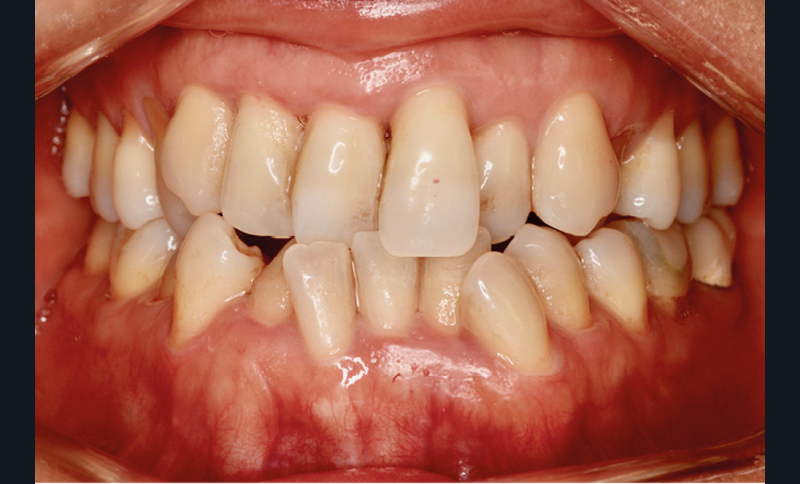

Présentation du cas (fig. 1 à 9)

Examen clinique

Mme J. présente une face longue, un profil droit avec un angle naso-labial fermé, une birétrocheilie et un menton bien dessiné. La ligne du sourire est basse, avec un sourire denté exposant peu les dents maxillaires, mais avec un parallélisme entre la lèvre inférieure et les bords libres des incisives maxillaires assez harmonieux.

Sur le plan squelettique, on retrouve une classe III de Ballard par hypomaxillie, dans un schéma facial hyperdivergent.

Sur le plan dentaire, la patiente est en classe III droite et gauche, canine et molaire de 6 mm, avec une occlusion inversée antérieure localisée à 11, 12 et 22. Elle présente une dysharmonie dents-arcades sévère, une agénésie d’une incisive mandibulaire est à signaler, et les troisièmes molaires ont été extraites à l’âge de 21 ans.

Au niveau fonctionnel, on note un bruxisme statique avec contact permanent entre les dents maxillaires et mandibulaires. La patiente présente des prématurités en relation centrée sur les incisives, le guidage en propulsion est perturbé et des interférences multiples sont retrouvées en latéralités droite et gauche.